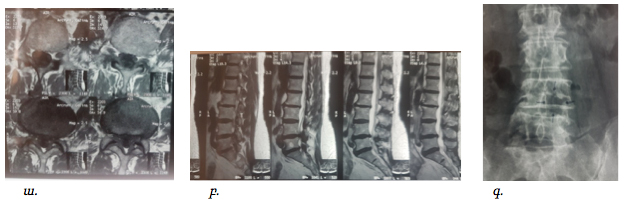

Նկ. 7 Նախա և հետվիրահատական հետազոտությունների համեմատականը

ա. Հիվանդի ՄՌՏ հետազոտում, առկա է ողնաշարային խողովակի արտահայտվածնեղացում L4-L5 մակարդակի (աքսիալ պրոեկցիա)

բ. Նույն հիվանդի ՄՌՏ հետազոտման պատկերը սագիտալ պրոեկցիայում

գ. ներվիրահատականռենտգեն հետազոտում՝ պատկերված է ՄՌՏ հետազոտմամբ ախտորոշված նեղացման տեղակայմանը համապատասխանող ոսկրային դեֆեկտը L4-L5 մակարդակի (ցույց է տրված սլաքով)